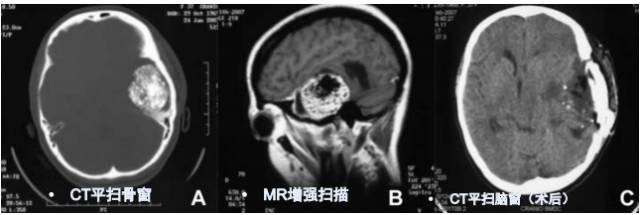

CT平扫(骨窗 脑窗)

病例:男性,30岁,头痛2月

CT平扫

病理结果:富于淋巴浆细胞型脑膜瘤,WHO I级

2、CT密度较高,钙化少见。MR T1信号等或稍低、T2信号稍低或稍高,增强后呈明显强化;病灶内或边缘可见T1低信号、T2高信号区,增强后不强化;病灶边缘可见广泛增厚的脑膜强化。肿瘤界限模糊,似炎症,累及皮层,瘤周水肿明显(特征性表现)。